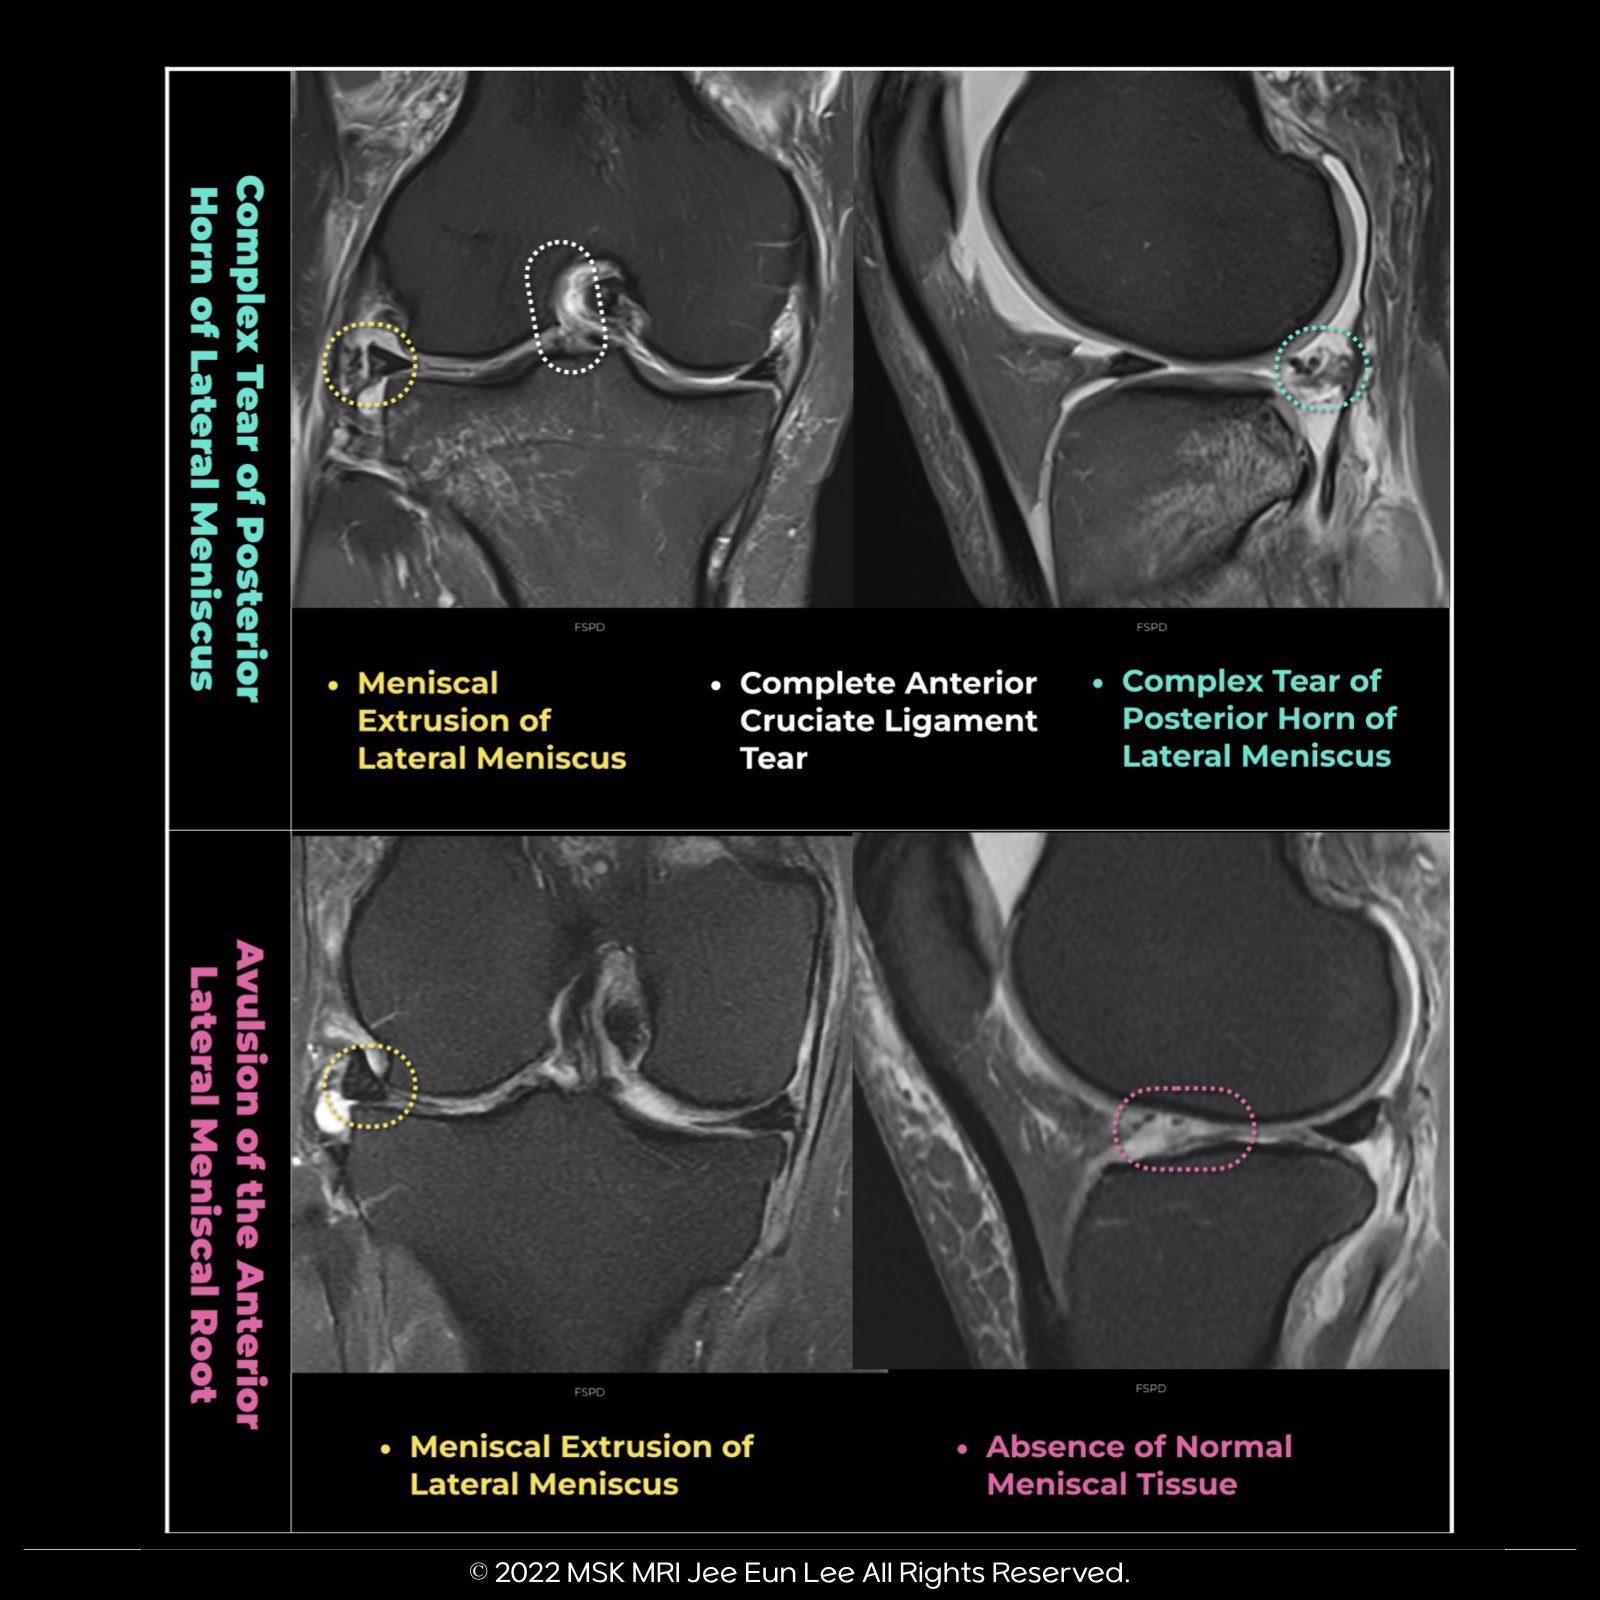

✅ Lateral Meniscal Extrusion Insights:

- Lateral meniscal extrusion greater than 1 mm is less common in patients with posterior root tears and ACL injury.

- Partial-width lateral root tears and meniscofemoral ligaments help stabilize the lateral meniscus.